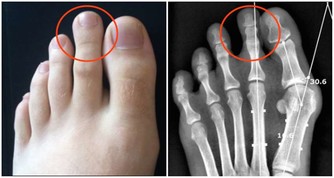

2、骨關節異常。一旦肺癌疾病發展到晚期,癌細胞分泌的特殊產物就會危及骨關節。肺癌細胞可產生某些特殊的內分泌激素(異源性激素)、抗原和酶,這些物質運轉作用於骨關節部位,而致骨關節腫脹疼痛,常累及脛、腓、尺、橈等骨及關節,指趾末端往往膨大呈杵狀指,x線攝片檢查可見骨膜增生。